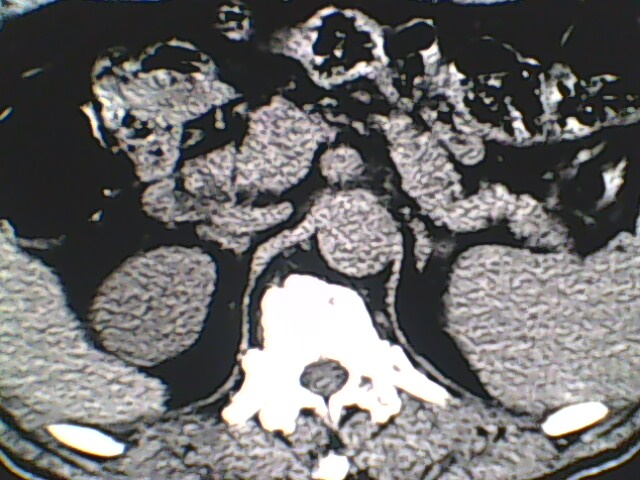

男,56岁,高血压,临床怀疑肾上腺问题,肝脏怎么那么高啊?能描述一下么?

右侧膈膨升,间位结肠,胸腰椎退行性骨关节病,右侧肾上腺可疑增生(图像颗粒太粗,窗太窄,不好看)。

支持 右侧膈膨升,间位结肠;胸腰椎退行性骨关节病;双侧肾上腺可疑增生。